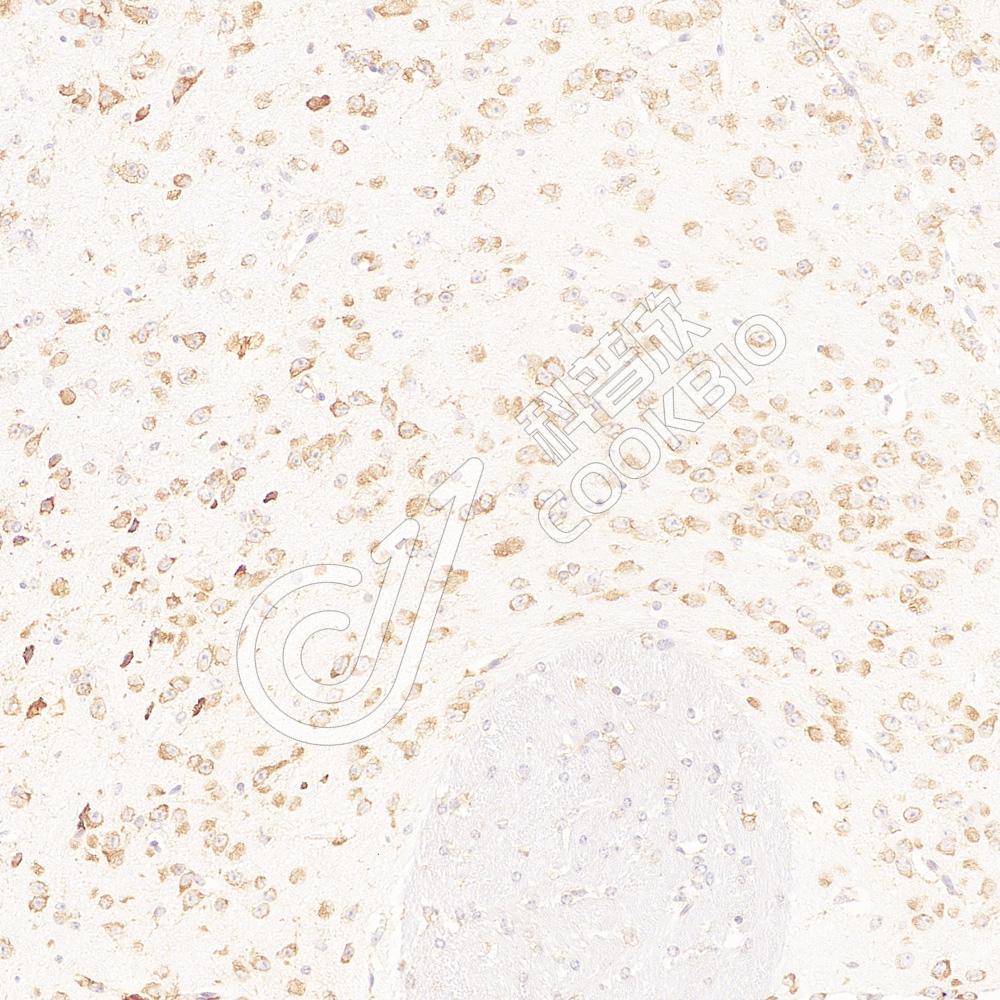

IHC检测GAP43蛋白(货号 K133285).

样品: 大鼠脑, 4%多聚甲醛 (货号KSG1101) 固定12-24小时.

抗原修复: 柠檬酸抗原修复液(干粉, pH 6.0) (KSG1201), 98℃, 20分钟.

—抗: 1: 600稀释, 4℃ 孵育过夜.

二抗: S-vision免疫组化多聚二抗(山羊抗兔),即用型 (货号KB3906), 室温孵育20分钟.